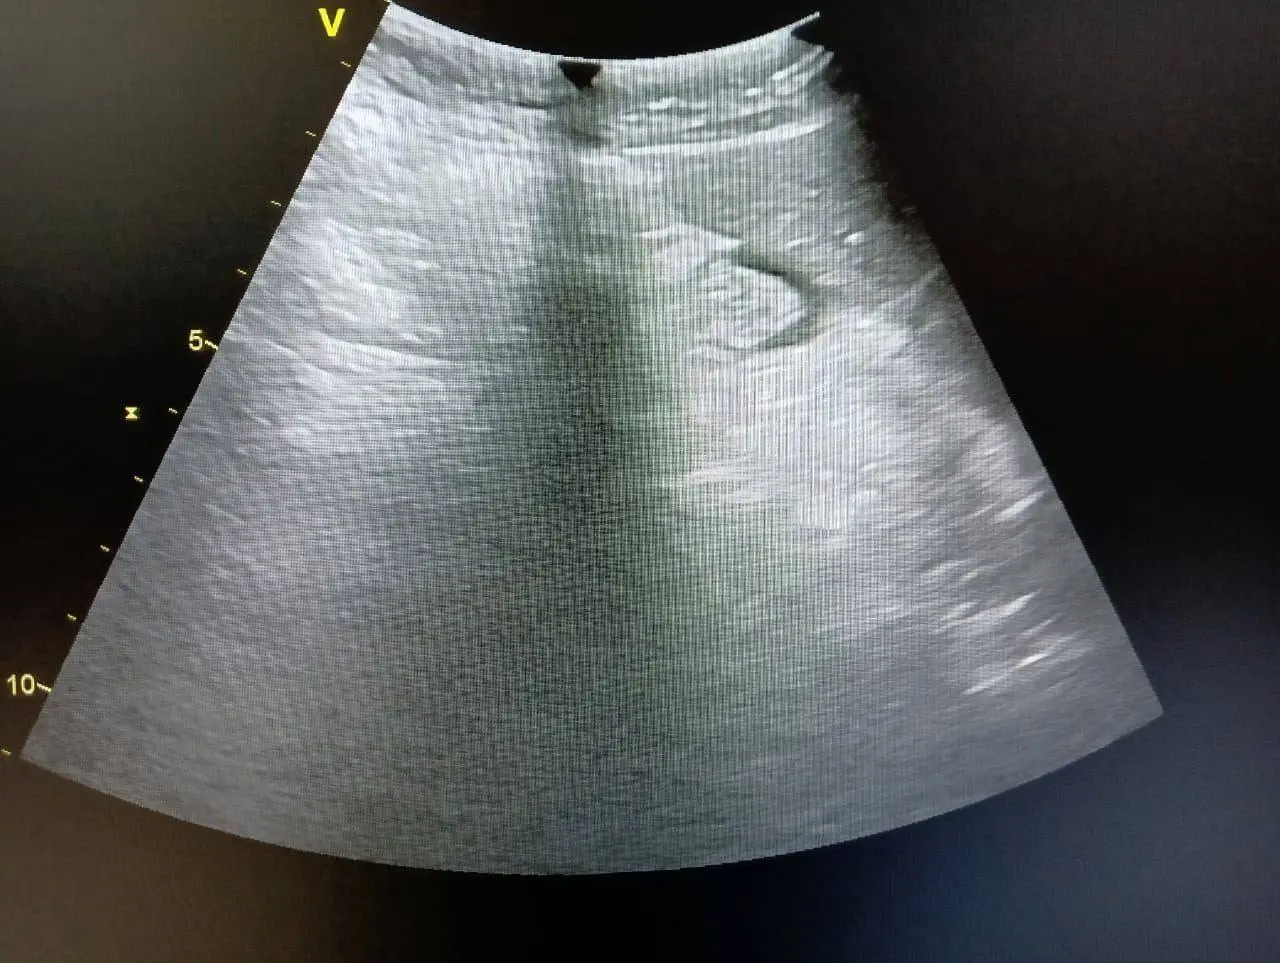

В сервисную службу Medford поступил УЗИ-аппарат Vivid T8 с жалобой на ухудшение качества изображения при работе с конвексным датчиком. При этом система проходила самотестирование без ошибок.

Снижение качества визуализации при отсутствии системных ошибок — одна из наиболее сложных диагностических задач в сервисе ультразвукового оборудования. В таких случаях стандартные тесты не выявляют проблему, и требуется анализ на уровне электронных компонентов.

Аппарат Vivid T8 демонстрировал типичный случай скрытого дефекта: система функционирует штатно, однако качество изображения не соответствует норме. Специалисты Medford провели детальную диагностику и локализовали проблему на уровне аналоговой части.